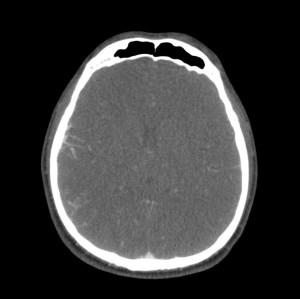

Se decide ingreso de la paciente para estudio y, ante el incremento de la cefalea y empeoramiento del estado general, se realiza nuevo TC de cráneo sin contraste. Veámos las imágenes.

1- TAC SIN CONTRASTE:

Se realiza para descartar otros procesos como infartos, tumores o infecciones.

- Signos directos: Cuerda Hiperdensa. En caso de trombo en las venas corticales, se observa el signo de la cuerda hiperdensa intraluminal. El trombo puede permancer hiperdenso 2 semanas para luego hacerse isodenso. La S y E de este signo son bajas.

- Signos indirectos: Cambios en el parénquima debido a la isquemia por perturbación del flujo venoso, produciéndose edema, infartos o hemorragias. Los infartos no hemorrágicos son las lesiones más frecuentes, suelen ser de localización subcortical, no sigue una distribución arterial y se localiza en las inmediaciones del seno afectado. Una afectación del SSS (el más frecuente) produce afectación bilateral en los territorios frontales, parietales y occipitales. Una afectación del ST afecta los lóbulos temporales. El seno recto afectado produce lesión profunda, en el tálamo. Los infartos hemorrágicos son menos frecuentes, se han descrito sangrados subdurales, subaracnoideos e incluso abiertos a ventrículos. El edema que se produce puede originar efecto masa con desplazamiento de la línea media e incluso disminución de ventrículos (dificil de valorar en jóvenes). La hidrocefalia marcada no se suele producir.